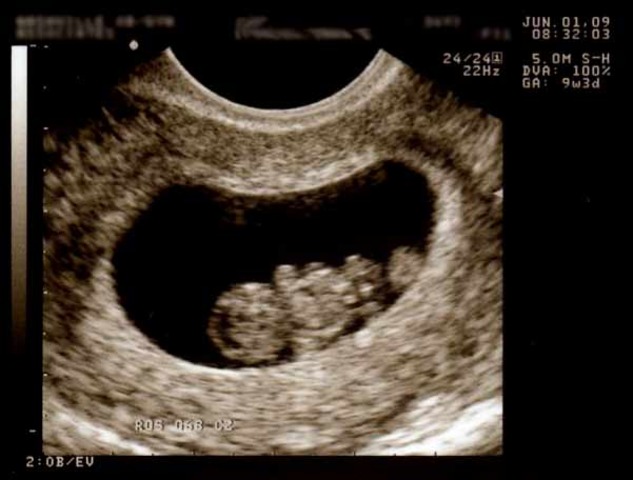

• week 12

week 12

The baby now has devolped facial features, such as a chin, nose, their facial profile, tooth buds. Their brain has fully devolped. Their vocal chords are now complete and they at times cry silently. The baby's eye lids are closed and will be until 7 months to protect the optical nerve. The fingers and toes have devloped soft nails and delicate hairs are beginning to grow on their heads. The baby's head makes up about half of the fetus size.

http://www.babycentre.co.uk/12-weeks-pregnant